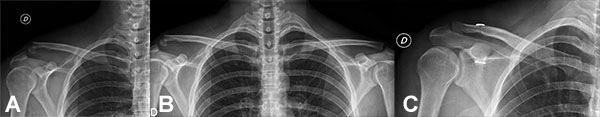

En la figura 7 podemos comparar la radiografías preoperatoria con el resultado definitivo de la reconstrucción artroscopia.

Figura 7: Resultado Final comparativo Rx Pre operatoria y Postoperatorio.